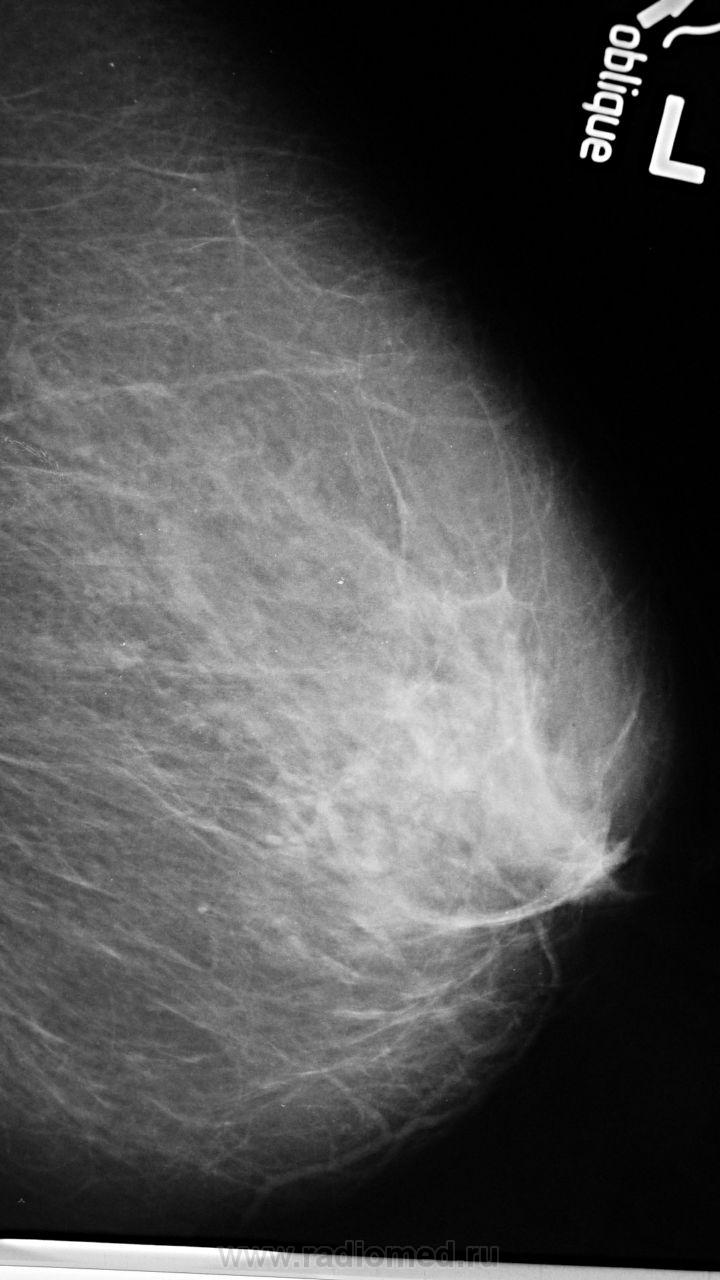

Ваше мнение о левой железе..?

образование жировой плотности - липома или жиросодержащая киста

Липома, с толстой фиброзной капсулой, должна пальпироваться. Для жиросодержащей кисты вроде как великовато.